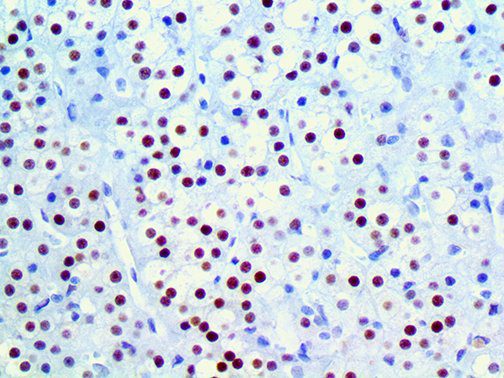

It is the ICU physician who is most likely to witness one of the deadliest manifestations of the abnormal immunological response, the cytokine storm syndrome (CSS). This response is also referred to by some as the cytokine release syndrome (CRS). CSS is characterized by continuous activation and expansion of macrophage and lymphocyte populations, which secrete large amounts of cytokines, causing the cytokine storm. This massive cytokine release is akin to hemophagocytic lymphohistiocytosis (HLH) disease, a syndrome characterized by initial unchecked and persistent activation of cytotoxic T lymphocytes and NK cells.

Clinical and laboratory manifestations of HLH include fever, enlarged liver and/or spleen, neurologic dysfunction, coagulopathy, liver dysfunction, cytopenias (i.e., low levels of erythrocytes, leukocytes, and/or platelets), hypertriglyceridemia, hyperferritinemia, hemophagocytosis, and eventually diminished NK cell activity as the immune system becomes progressively paralyzed. HLH can be familial (primary HLH) or secondary to another disease process (sHLH), such as rheumatic disease, in which it is referred to as macrophage activation syndrome (MAS, characterized by elevated ferritin).